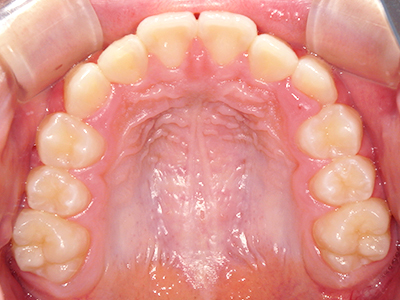

歯並びの相談に来られるお子様は、口呼吸をしているケースが多く、これが歯並びに大きな影響を与えています。

↓ - 頬の圧力が上の歯列にかかりやすくなる

↓ - 上あごが狭くなる

↓ - 下あごが狭くなる・下あごの位置が悪くなる

↓ - さまざまな不正咬合が生じる

ないき歯科クリニックでは、上あごの成長不足を補い、鼻呼吸を獲得しつつ歯列を整え、将来のお口をより健康な状態にすることをゴールに定める矯正治療をおこなっています。